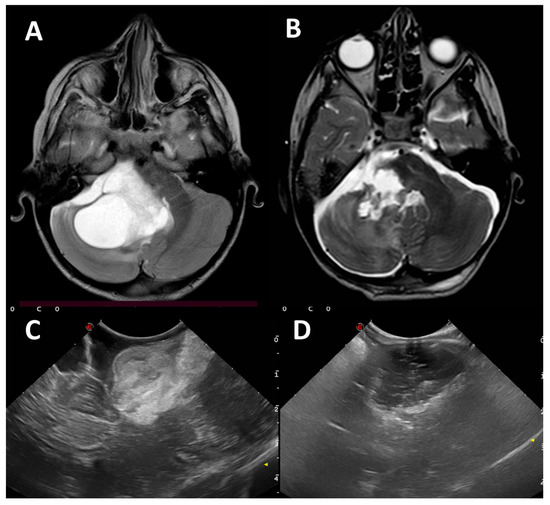

NF1 with Multiple Cardiac Structural Abnormalities Leading to Cerebral Infarction

by Jingwei Ye, Yiyi Jiang, Hanmin Wang and Dan Wang

Diagnostics 2026, 16(1), 163; https://doi.org/10.3390/diagnostics16010163 - 4 Jan 2026

Background/Objectives: Neurofibromatosis type 1 (NF1) is an autosomal dominant disorder driven by mutations in the NF1 gene, whose pathogenesis centers on the loss of neurofibromin function and subsequent hyperactivation of the RAS/MAPK pathway. Notably, to the best of our knowledge and following [...] Read more.

Background/Objectives: Neurofibromatosis type 1 (NF1) is an autosomal dominant disorder driven by mutations in the NF1 gene, whose pathogenesis centers on the loss of neurofibromin function and subsequent hyperactivation of the RAS/MAPK pathway. Notably, to the best of our knowledge and following a systematic literature search conducted by our research team, no cases of NF1 complicated by severe cardiac structural abnormalities that ultimately lead to cerebral infarction have been reported to date. Thus, it is of paramount importance to avoid missed diagnosis by performing comprehensive cardiac-related examinations in patients with NF1. Case Presentation: A 20-year-old male patient diagnosed with NF1 presented with right-sided limb weakness and was initially identified with cerebral infarction. To clarify the underlying etiology, a comprehensive clinical evaluation was performed, including cardiac imaging assessments (to characterize cardiac structural changes) and whole-exome sequencing (to identify the presence of procoagulant gene mutations). Comprehensive evaluation revealed a spectrum of cardiac structural abnormalities in the patient: aortic valve prolapse with severe regurgitation, non-infective vegetations on the aortic valve leaflets, mild-to-moderate mitral regurgitation, left ventricular hypertrophy and dilation, and left atrial dilation. Whole-exome sequencing detected exclusively a pathogenic variant in the NF1 gene, with no other pathogenic/likely pathogenic variants or thrombophilia-associated polymorphisms being found. Laboratory investigations ruled out infectious etiologies, supporting the notion that NF1-mediated cardiac structural and developmental anomalies are the primary driver of cardiac vegetation formation, given the absence of other identified contributing factors; embolization of one such vegetation ultimately led to both splenic and cerebral infarction. Conclusions: This case emphasizes the necessity of implementing early and proactive cardiac evaluations in patients with NF1. Additionally, for NF1 individuals—particularly those presenting with suggestive vascular or cardiac symptoms—a comprehensive multifactorial assessment of thrombotic risk is critical. Collectively, maintaining clinical vigilance for cardiac abnormalities in NF1 patients and avoiding diagnostic oversight is essential to reduce life-threatening risks. Full article